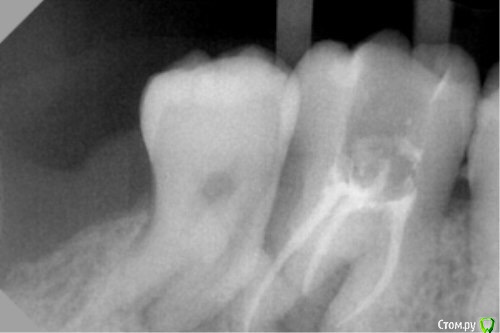

dr.Dre Опубликовано 27 апреля, 2016 Поделиться Опубликовано 27 апреля, 2016 Добрый день коллеги,26 зуб коффердам,много хлорки,на неделю Пульпосептин,гуттаперча + акросил.Между 26,27 ясенный карман.Какой прогноз данного зуба,и что делать с 27,1 степень подвижности. Ссылка на комментарий

Ирина Игоревна Опубликовано 27 апреля, 2016 Поделиться Опубликовано 27 апреля, 2016 Мне кажется, или на втором снимке похоже на перелом апикальной части корня? Ссылка на комментарий

dr.Dre Опубликовано 27 апреля, 2016 Автор Поделиться Опубликовано 27 апреля, 2016 Мне кажется, или на втором снимке похоже на перелом апикальной части корня?Сам только что увидел Ссылка на комментарий

St. Опубликовано 27 апреля, 2016 Поделиться Опубликовано 27 апреля, 2016 Ирина Игоревна сказал(а) 27 Апр 2016 - 16:18: Мне кажется, или на втором снимке похоже на перелом апикальной части корня? Сам только что увидел Не обязательно. Это может накладываться уровень кости межпроксимально. 2 Ссылка на комментарий

dantist_movani Опубликовано 27 апреля, 2016 Поделиться Опубликовано 27 апреля, 2016 Перелом 2.6. Попробуй Кт на всякий случай. Ссылка на комментарий

___49___ Опубликовано 28 апреля, 2016 Поделиться Опубликовано 28 апреля, 2016 (изменено) По снимкам вижу деструктивные изменения кости начиная от дистальной стенки 6ого проходящие между неб. и дист.щеч. корнем (что похоже на перелом, но его нет скорее всего) в область трифуркации и далее до апексов.. ... как не печально, прогноз - неблагоприятный. это все касаемо 6ки. Изменено 28 апреля, 2016 пользователем ___49___ 1 Ссылка на комментарий